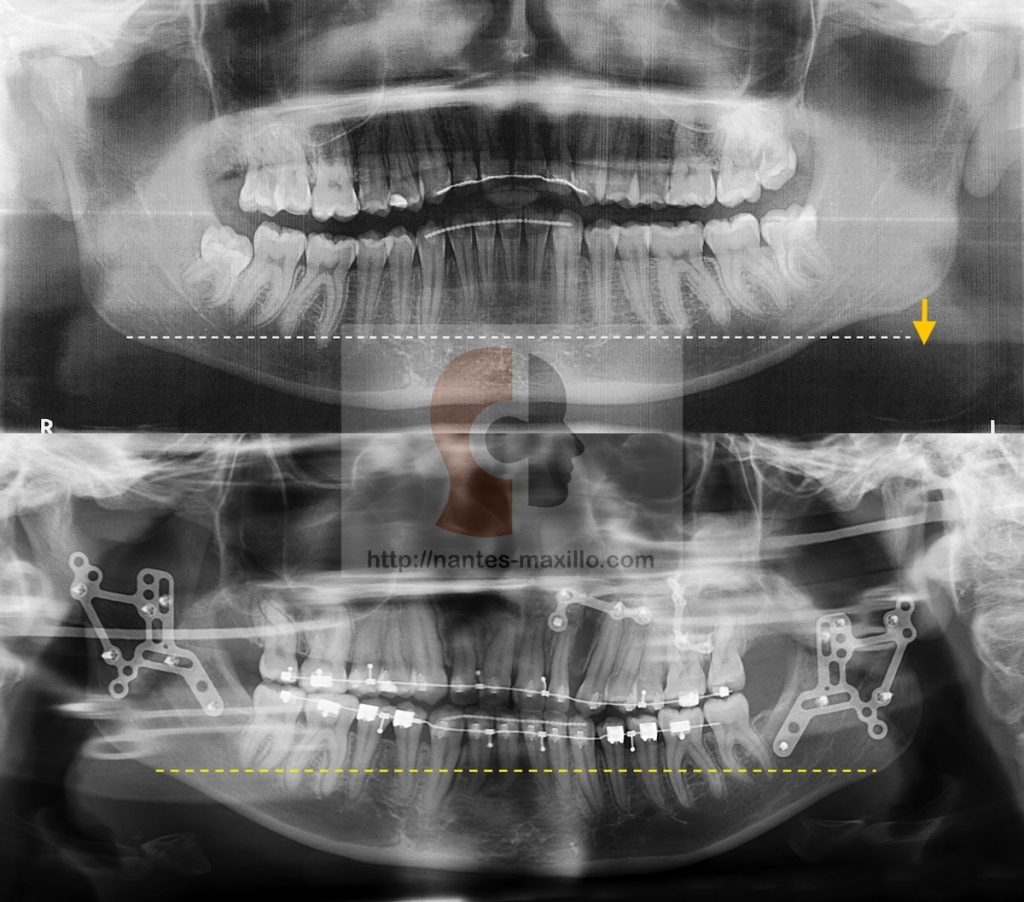

On voit ici sur le panoramique l’horizontalisation de l’angle mandibulaire,

(la chirurgie a associé une ostéotomie segmentaire maxillaire Gauche d’abaissement à une ostéotomie haute bilatérale d’avancée, et d’abaissement de l’angle gauche.)

Hypercondylie droite opérée par une condylectomie par un abord externe, associée à un abaissement de l’angle mandibulaire Gche, remontée de l’angle mandibulaire droit, et une horizontalisation du maxillaire